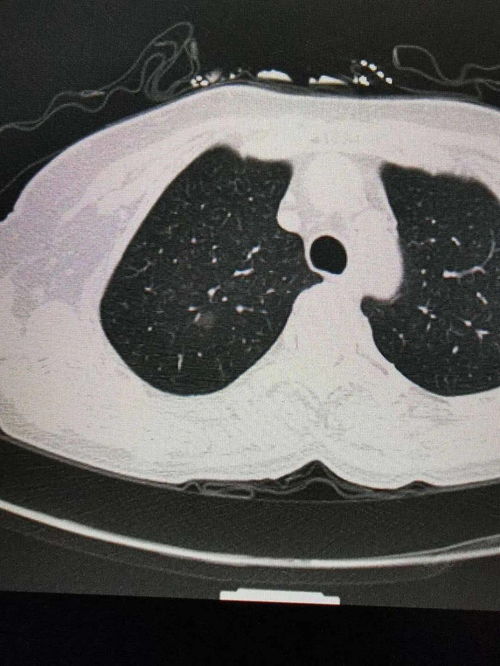

在社区卫生服务中心的年度体检报告上,“胸部X光片未见明显异常”这一行字,曾像一枚定心丸,让王建国(化名)老人和他的家人安稳度过了又一年。这位75岁的退休教师,生活规律,注重养生,并且有着超过十五年的“完美”体检记录——每年一次的单位或社区体检,胸片检查是雷打不动的项目。他常对老友笑谈:“我年年都给肺拍‘年检照片’,放心得很。” 就在一次因持续干咳和轻微气短就医,接受了一次低剂量螺旋CT检查后,诊断结果却如晴天霹雳:右肺门区发现一个约3厘米的肿块,伴有多发纵隔淋巴结转移,临床分期已属晚期(IIIB期)。这个结果让患者、家属乃至首诊医生都陷入了深深的困惑与震惊:“每年都拍胸片,怎么还会漏掉?而且一发现就是晚期?”

胸片是三维胸部结构在二维平面上的重叠投影。心脏、纵隔大血管、膈肌、肋骨等组织器官会与肺组织影像前后、左右重叠。早期肺癌,尤其是位于这些重叠区域(如肺门后方、心脏后方、脊柱旁、膈肌穹窿顶部)的病灶,极易被正常组织的致密影所掩盖,从而成为影像学上的“盲区”。王老先生肿瘤所在的肺门区,正是支气管、大血管进出肺脏的枢纽,结构复杂,重叠严重,是胸片漏诊的“重灾区”。

胸片对组织密度的分辨率有限。通常,只有当肺部结节生长到足够大(一般直径大于1厘米,甚至更大),且密度较高、与周围肺组织形成足够对比时,才能在胸片上被清晰辨识。许多早期肺癌表现为磨玻璃样结节(GGN)或混合磨玻璃结节,其密度淡薄,如同云雾,在胸片上极易被忽略或误认为炎症、纤维灶。胸片难以清晰显示结节的细微结构,如分叶、毛刺、胸膜凹陷等恶性征象,而这些恰恰是低剂量螺旋CT(LDCT)的强项。

胸片报告上的“未见明显异常”,其准确解读应为“在本次胸片检查的敏感度范围内,未发现达到一定大小和密度的可疑占位”。它绝不等于“肺部绝对健康,没有早期肺癌”。将胸片作为肺癌筛查工具,其敏感性(发现真阳性的能力)远低于低剂量螺旋CT,大量研究证实,使用胸片进行筛查,并不能有效降低肺癌的死亡率。这正是王老先生悲剧的技术根源:他年复一年依赖的,是一件“筛眼”过大的工具。